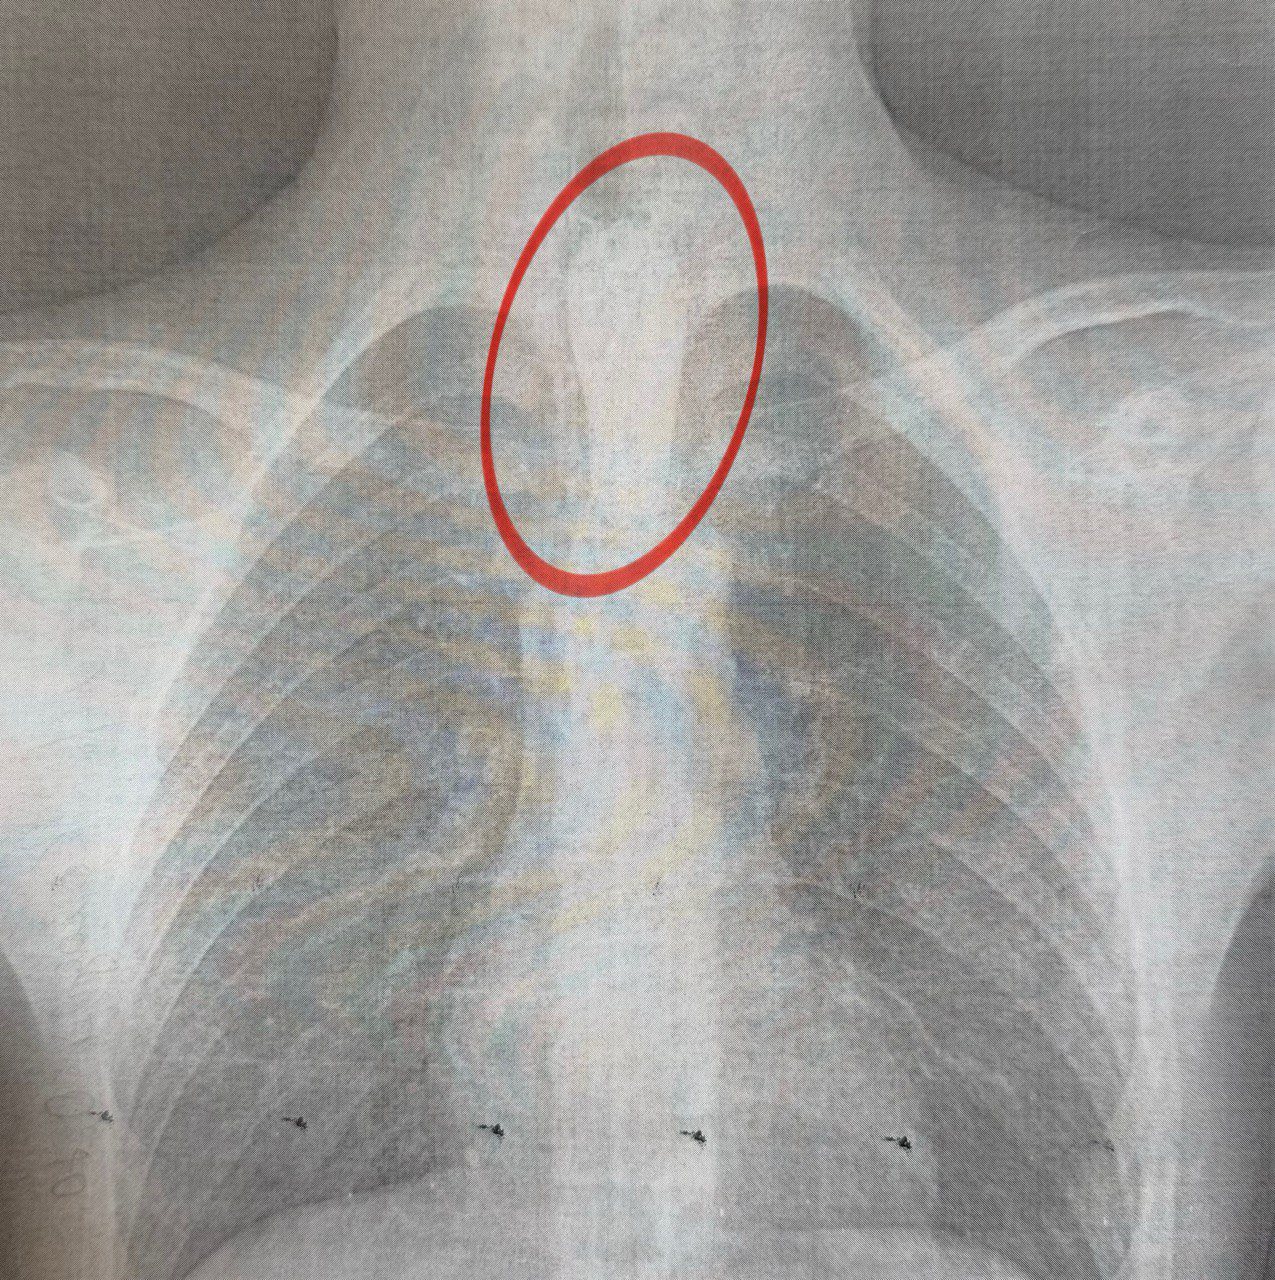

Как рассказал торакальный хирург Александр Колодий, кусок мяса остановился на одном из естественных сужений пищевода — у аорты, что значительно усложнило ситуацию.

Ночью ребенка доставили в операционную, где команда медиков провела ригидную эзофагоскопию — сложное вмешательство по удалению инородного тела из пищевода. Процедура длилась около часа. Чтобы не травмировать стенки органа, хирурги доставали кусок мяса поэтапно.

"Это очень деликатная хирургическая работа. Необходимо действовать осторожно, чтобы не вызвать перфорацию пищевода", — пояснил Колодий.